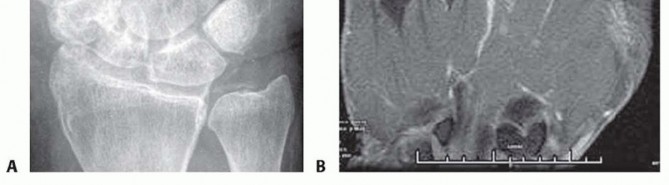

Radiographic evaluation begins with orthogonal plain films. Early in the disease process, radiographs are typically normal or demonstrate only subtle soft tissue swelling and joint space widening secondary to effusion. However, they are crucial for ruling out retained radiopaque foreign bodies, fractures, or underlying chronic arthropathies. The presence of chondrocalcinosis, for instance, may suggest pseudogout, though crystalline arthropathy and septic arthritis can coexist.

Image

When the diagnosis remains equivocal, or to assess the extent of soft tissue and osseous involvement, Magnetic Resonance Imaging (MRI) is the modality of choice. MRI provides unparalleled soft tissue contrast, readily identifying joint effusions, synovial hypertrophy, and early marrow edema indicative of impending osteomyelitis. T2-weighted fluid-sensitive sequences will dramatically highlight the intra-articular purulence and surrounding inflammatory edema.